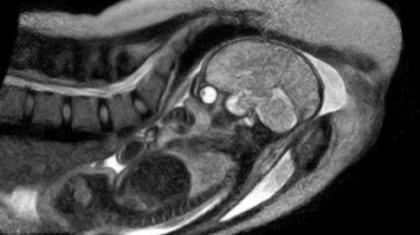

Γιατροί σε νοσοκομείο του Βερολίνου έγραψαν ιστορία, καθώς τραβούσαν φωτογραφίες μέσω μαγνητικού τομογράφου την ώρα που πραγματοποιούνταν το θαύμα της γέννησης.